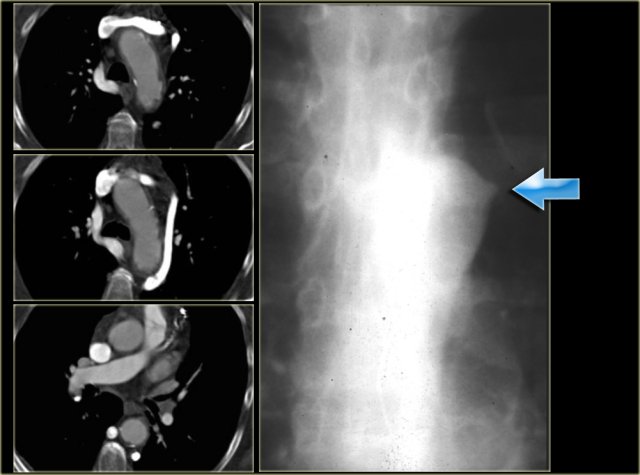

On the left a 78 year old woman with dysphagia.

There is consolidation in the right upper lobe, maybe due to aspiration.

There is a dilated vessel that compresses the esophagus and it originates from the left-sided aorta, i.e. an aberrant right subclavian artery.

On the left the same patient with dilated aberrant right subclavian artery.

Coronal reconstruction.